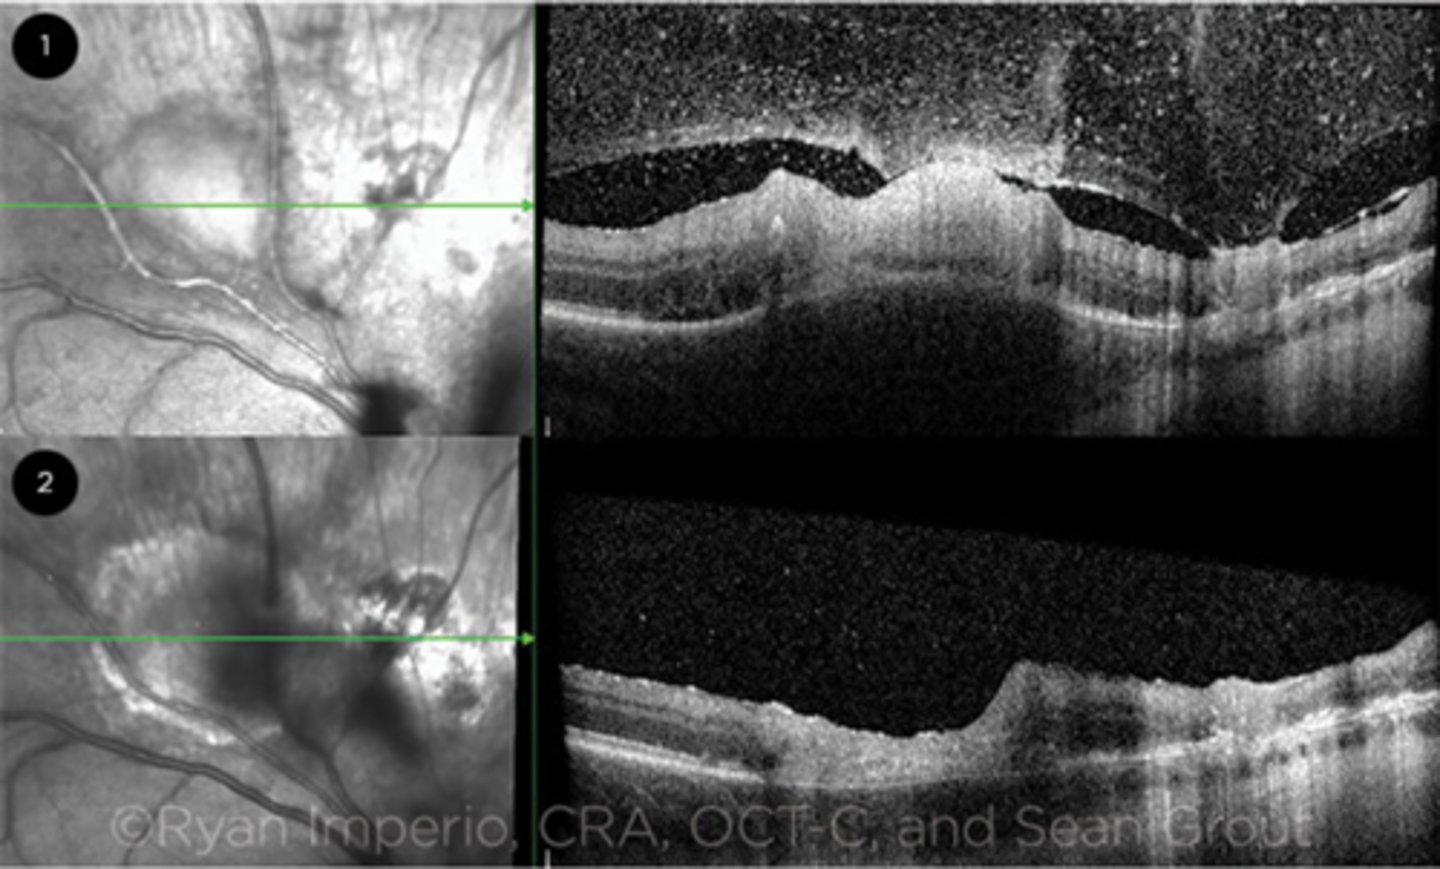

What is seen in toxoplasmosis with OCT?

acute = retinitis = inflam, thickening of layers

acute = vitritis = dots and haze vitreous

chronic = necrotizing atrophy = scarring, thinning